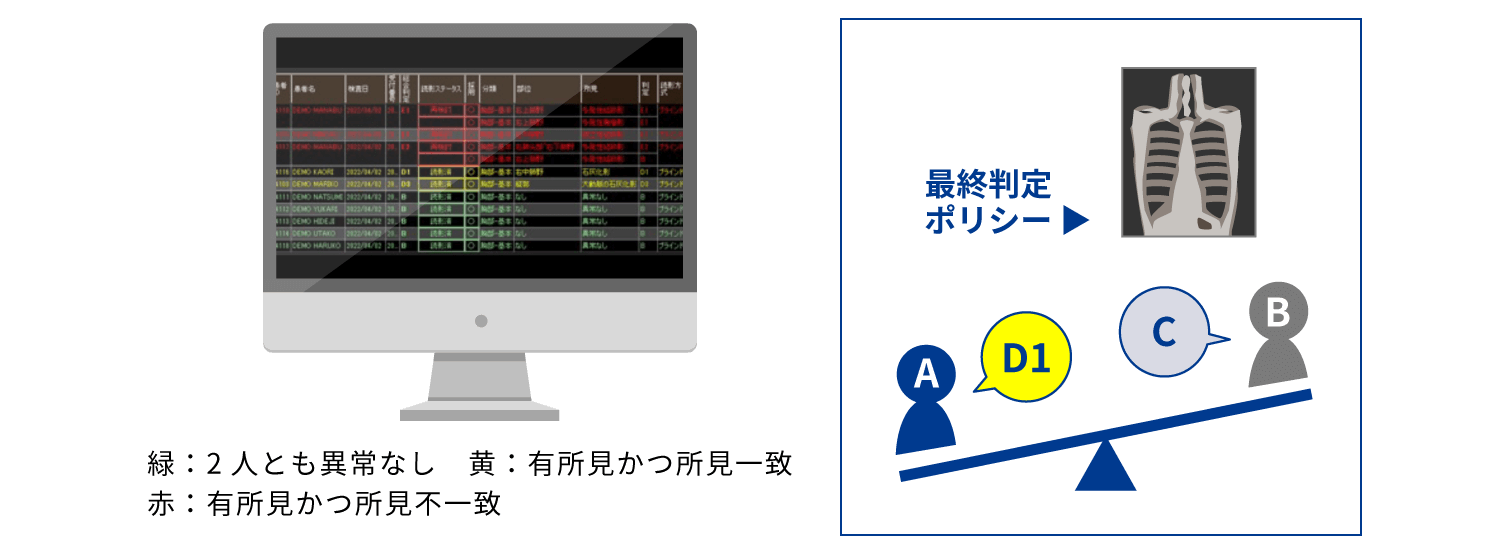

事務業務の人的ミス・負担を軽減したい!

- 連番撮影のマッチングを自動化し、作業時間を大幅削減

- ボタン一つで二重読影結果を統合。数秒で最終結果確定へ

- 画像登録から結果出力までの進捗状況を、一覧画面で簡単に確認

- 基幹健診システムと連携することで、結果の転記も不要

二重読影結果の一括自動判定

判定結果を色分表示

読影の進捗状況を一覧画面で管理

健診種別を細かく設定して管理可能

煩雑だった業務が数秒で完了!

人的ミスや業務スタッフの負担を大幅に軽減します。